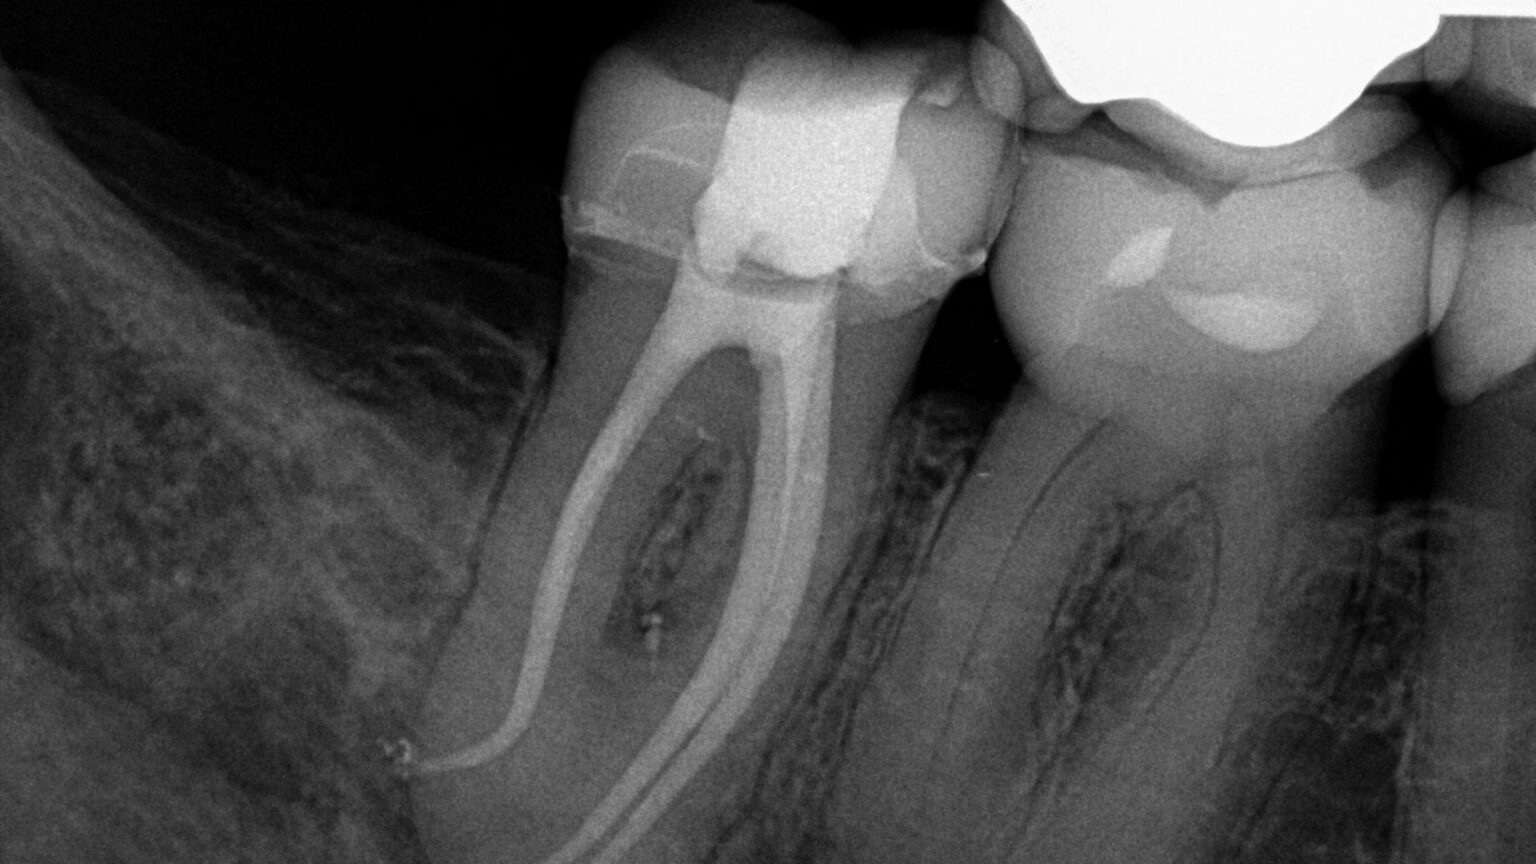

Final Endodontic Irrigation With 70 Ethanol . Results irrigation with 70% ethanol presented a significantly higher percentage of clean root canal walls and a higher depth of clean. The aim of this study was to evaluate the efficacy of different lengths of time of passive ultrasonic irrigation (pui) in removing calcium. Irrigation with 70% ethanol presented a significantly higher percentage of clean root canal walls and a higher depth of clean dentinal tubules. Irrigation with 70% ethanol presented a significantly higher percentage of clean root canal walls and a higher depth of clean dentinal tubules. Irrigation with endovac and piezoflow™ ultrasonic irrigation systems improved the removal of the intracanal medicament resulting in cleaner root. Irrigation with 70% ethanol presented a significantly higher percentage of clean root canal walls and a higher depth of clean dentinal tubules when. The present study demonstrated that 70% ethanol enhanced calcium hydroxide removal from the apical root third compared with 2.5%. Irrigation with 70% ethanol presented a significantly higher percentage of clean root canal walls and a higher depth of clean.

Irrigation with 70% ethanol presented a significantly higher percentage of clean root canal walls and a higher depth of clean. The present study demonstrated that 70% ethanol enhanced calcium hydroxide removal from the apical root third compared with 2.5%. Irrigation with 70% ethanol presented a significantly higher percentage of clean root canal walls and a higher depth of clean dentinal tubules. Results irrigation with 70% ethanol presented a significantly higher percentage of clean root canal walls and a higher depth of clean. Irrigation with 70% ethanol presented a significantly higher percentage of clean root canal walls and a higher depth of clean dentinal tubules when. The aim of this study was to evaluate the efficacy of different lengths of time of passive ultrasonic irrigation (pui) in removing calcium. Irrigation with 70% ethanol presented a significantly higher percentage of clean root canal walls and a higher depth of clean dentinal tubules. Irrigation with endovac and piezoflow™ ultrasonic irrigation systems improved the removal of the intracanal medicament resulting in cleaner root.

Final Endodontic Irrigation With 70 Ethanol Irrigation with endovac and piezoflow™ ultrasonic irrigation systems improved the removal of the intracanal medicament resulting in cleaner root. Irrigation with 70% ethanol presented a significantly higher percentage of clean root canal walls and a higher depth of clean dentinal tubules. Results irrigation with 70% ethanol presented a significantly higher percentage of clean root canal walls and a higher depth of clean. Irrigation with 70% ethanol presented a significantly higher percentage of clean root canal walls and a higher depth of clean dentinal tubules when. Irrigation with 70% ethanol presented a significantly higher percentage of clean root canal walls and a higher depth of clean. The aim of this study was to evaluate the efficacy of different lengths of time of passive ultrasonic irrigation (pui) in removing calcium. Irrigation with 70% ethanol presented a significantly higher percentage of clean root canal walls and a higher depth of clean dentinal tubules. Irrigation with endovac and piezoflow™ ultrasonic irrigation systems improved the removal of the intracanal medicament resulting in cleaner root. The present study demonstrated that 70% ethanol enhanced calcium hydroxide removal from the apical root third compared with 2.5%.